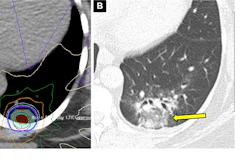

PDA has poor survival rates, as it's often diagnosed late -- in the absence of symptoms and visible tissue changes -- and it rapidly progresses, the researchers explained. They created an AI framework called Radiomics-based Early Detection MODel (REDMOD), specifically designed to identify subtle tissue texture patterns (that is, radiomics) of very early pancreatic cancer, which standard CT scans can't always see. As well, REDMOD delineates the borders of the pancreas from surrounding tissue/organs, thus eliminating the need for this to be done manually, according to the group.

Mukherjee and colleagues used REDMOD with abdominal CT scans from 219 patients who showed no evidence of disease after radiologist review but who were subsequently diagnosed with pancreatic cancer. In the majority of patients (40%), the cancer manifested in three to 12 months, while in 35% it appeared in 12 to 24 months and in 25% in more than 24 months. The investigators compared the scans from the 219 patients to 1,243 patients who did not develop pancreatic cancer up to three years later (matched by age, sex, and scan date).

They found that REDMOD could identify the "invisible" signature of preclinical pancreatic ductal adenocarcinoma an average of 475 days before clinical diagnosis -- a result that could significantly improve patient outcomes, they said in a statement released by the journal.